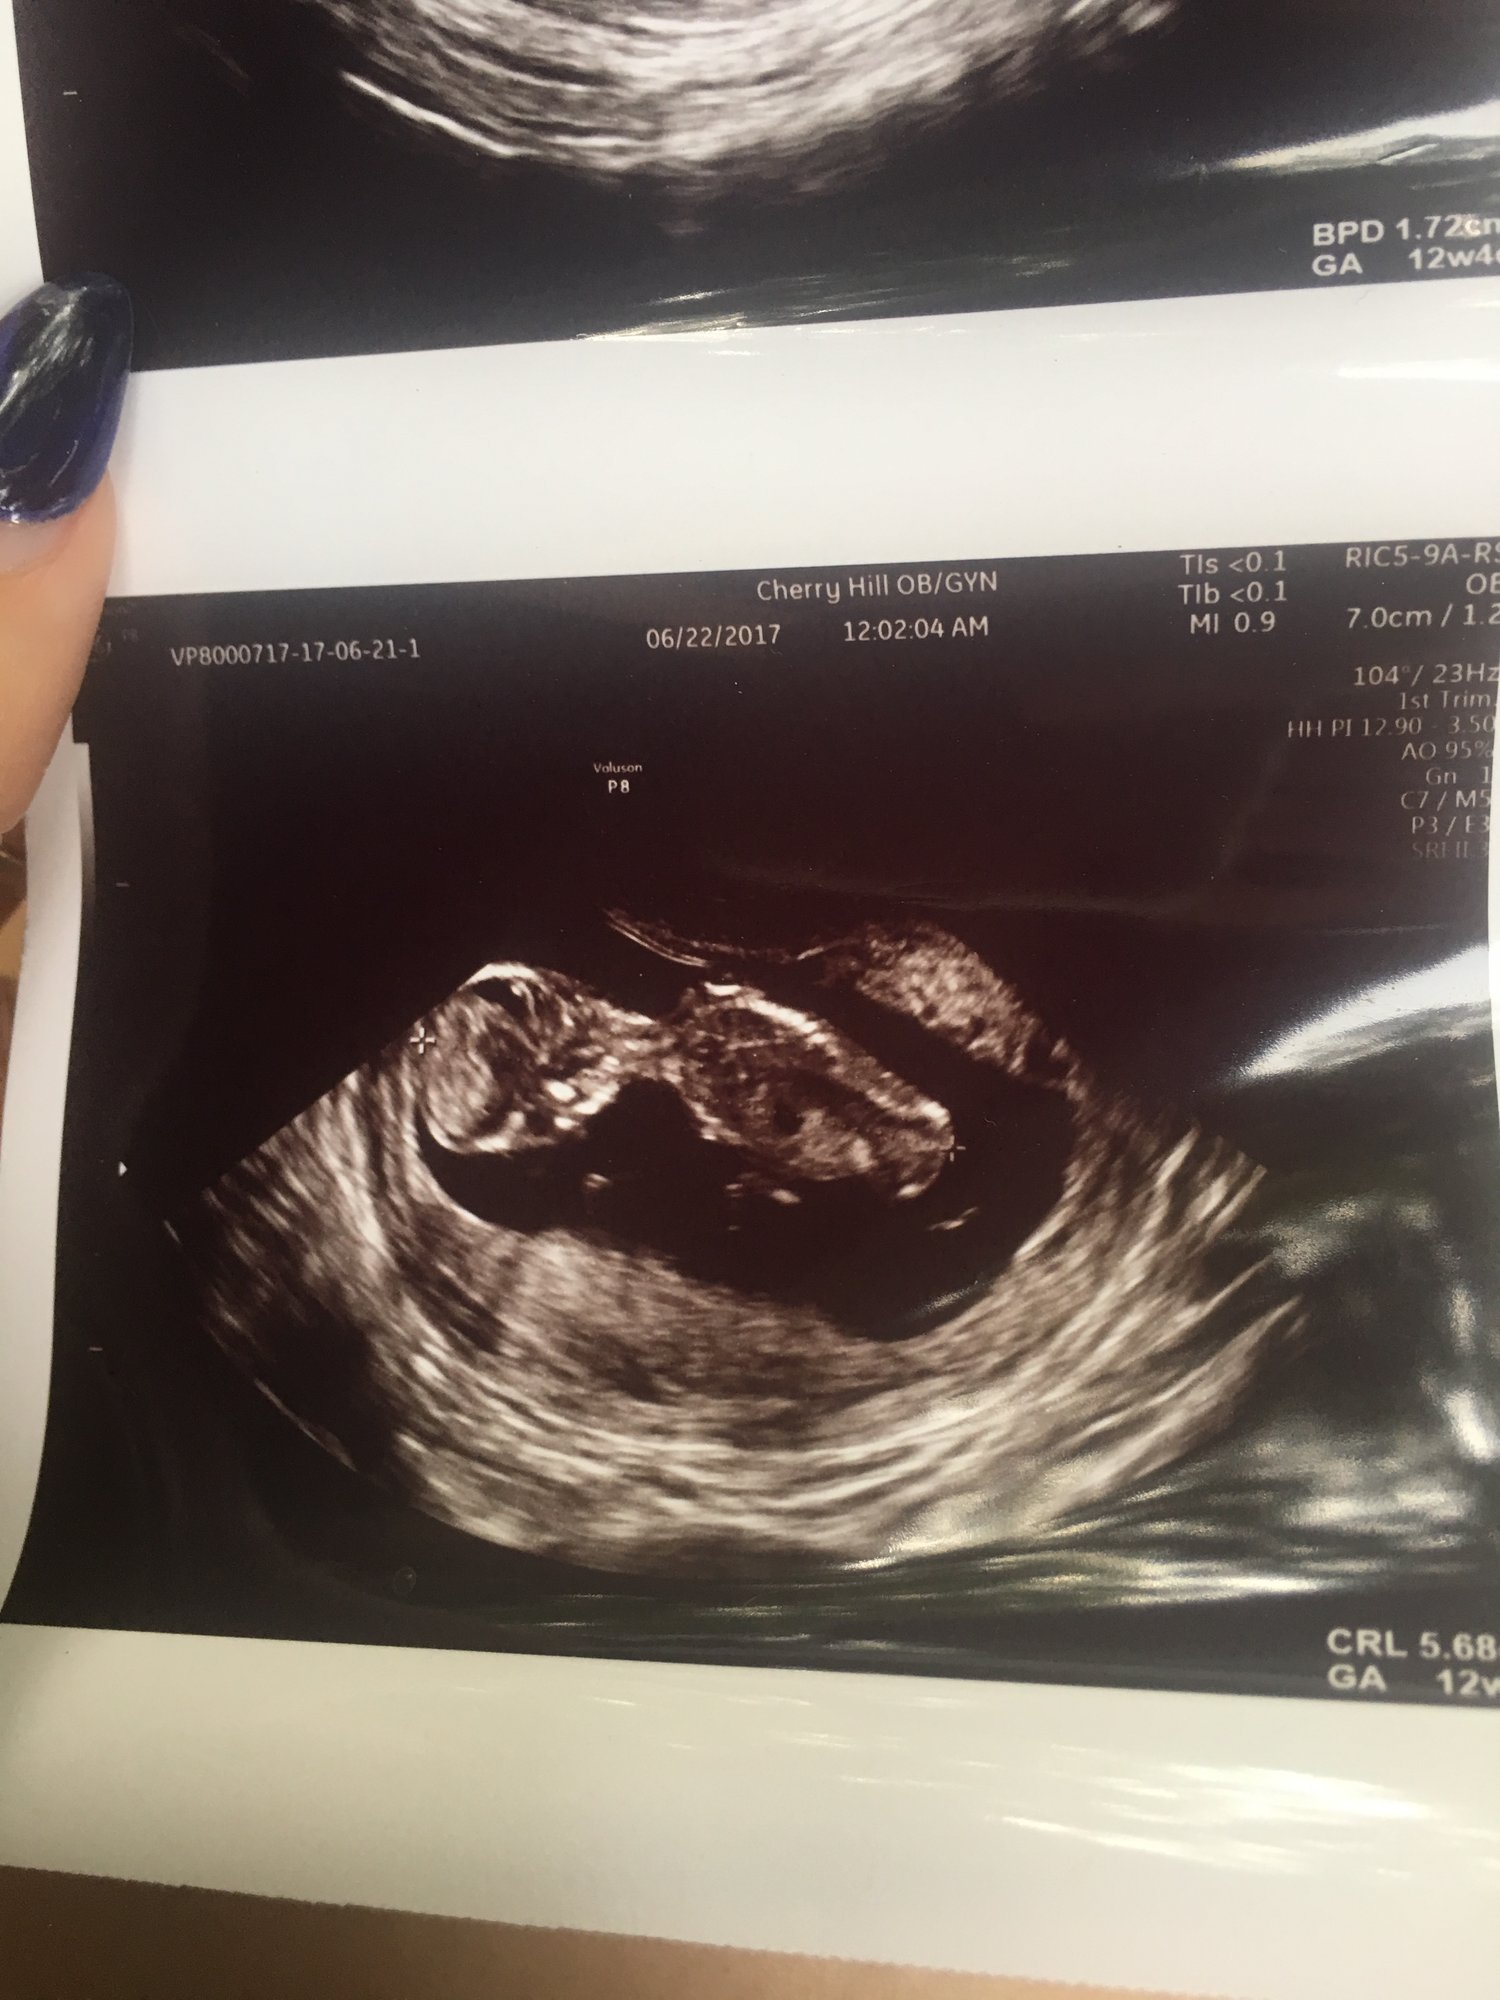

12w3d NT scan. NT results were good (as expected since NIPT was good). Pretty cool that you can see the jaws opening and closing, with what I guess are tooth buds, huh?

And so amazing (except for the tech with a pretty crappy attitude but I understand they might need to be a bit detached).

I swear that the images in real time were very much like a real baby rather than the blobby image. Due date was moved up a day, but we're still going with Jan. 14. Whole family is now calling the baby, "The Blob". Haha!